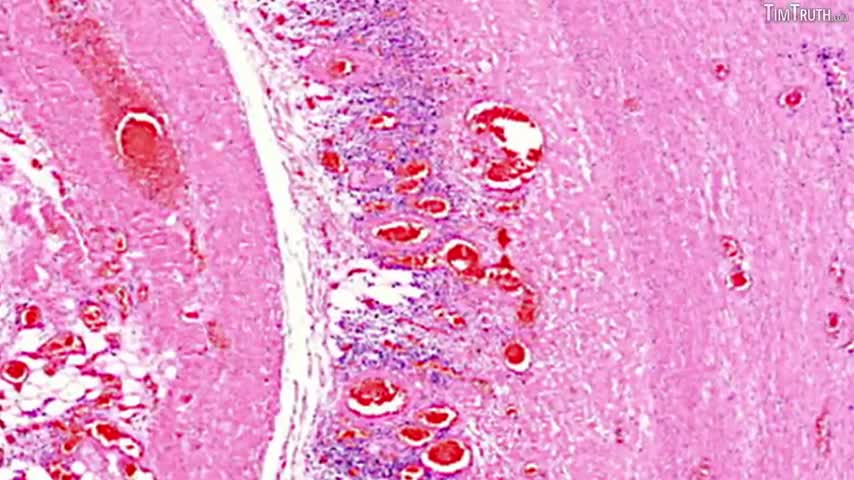

DR BHAKDI & DR PALMER'S COMPELLING EVIDENCE THAT C19 VACCINES CAUSE VASCULAR AND ORGAN DAMAGE